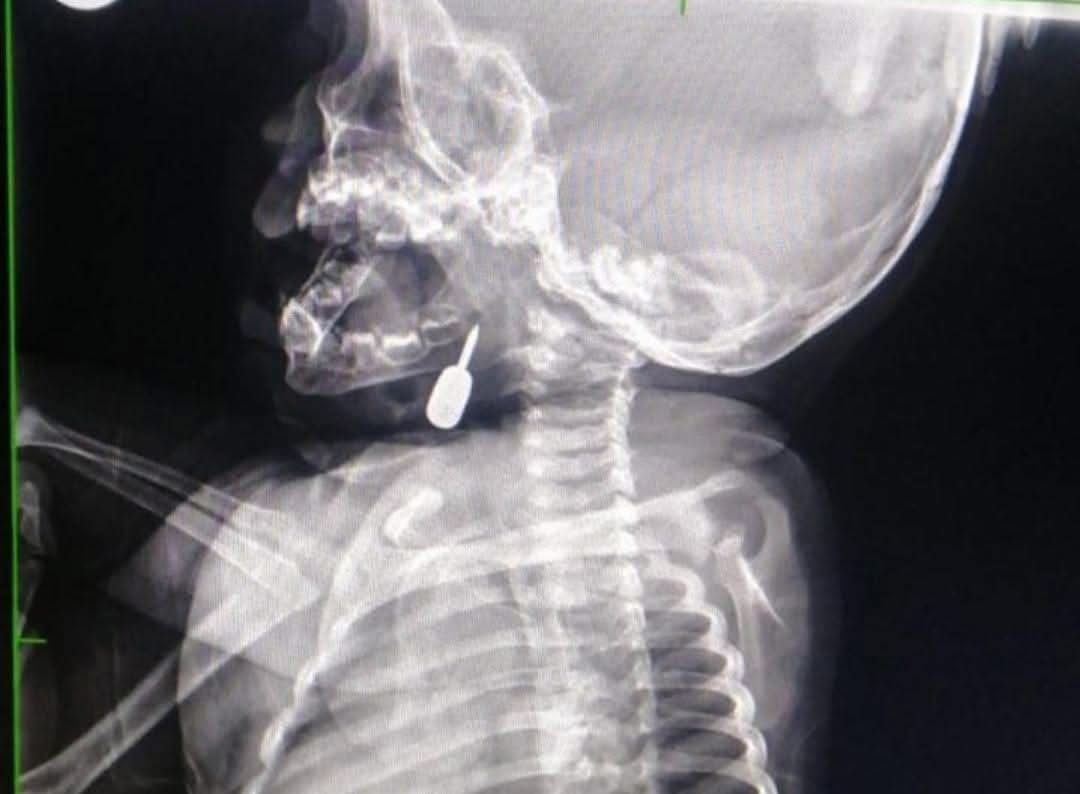

أخبار اليوم - تمكّن أخصائي الأنف والأذن والحنجرة الدكتور محمود السبول من إجراء عملية فتح رغامى تُعد الأولى من نوعها في مستشفى الملكة رانيا العبدالله، وقد تمت بنجاح.

وفي تدخل طبي عاجل، أنقذ الدكتور السبول حياة طفل يبلغ من العمر أحد عشر شهراً، بعد أن وصل إلى قسم الطوارئ وهو يعاني من حالة اختناق حادة نتيجة وجود جسم معدني عالق في منطقة الحنجرة. وقد تم استخراج الجسم بنجاح، مما أسهم في إنقاذ حياة الطفل.